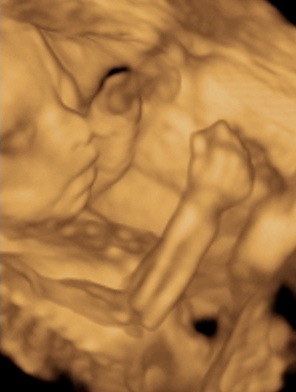

A 3D-s babafotok meg mindig lenyugoznek, nem birok betelni veluk. SZomoruan olvasom, hogy mennyi aprobb-nagyobb kellemetlensegetek van, de szerintem mindenki nagyon szuperul halad, ugyesek vagytok...le a kalappal foleg a dolgozok, vagy mar babasok elott! majd most teszek fel kepeket es is Azzurrarol, bar mar tobb, mint 5 hete keszultek, de ujabbak mar nem lesznek, es mivel kimaradtam abban az idoszakban, most potolom. Az tuti, hogy ezentul mindenkinek javasolni fogom a 4D-t ilyen koran is (22+1 hetesen voltunk), mert bar csimota ducibb volt az atlagnal es mar akkor volt rajta jo adagnyi izom (ez is a napi 1 l tej

), de egy sovanyabb baba is csodaszep szerintem...mindent el lehet mondani, csak azt nem, hogy csontkollekciok lennenek. Osszessegeben ugy nez ki, hogy ram hasonlit, de a szemoldokcsontja es a szaja az egy az egyben a parome...szerencsere...neki az sokkal szebb...remelem, haj-ugyben is ra ut majd